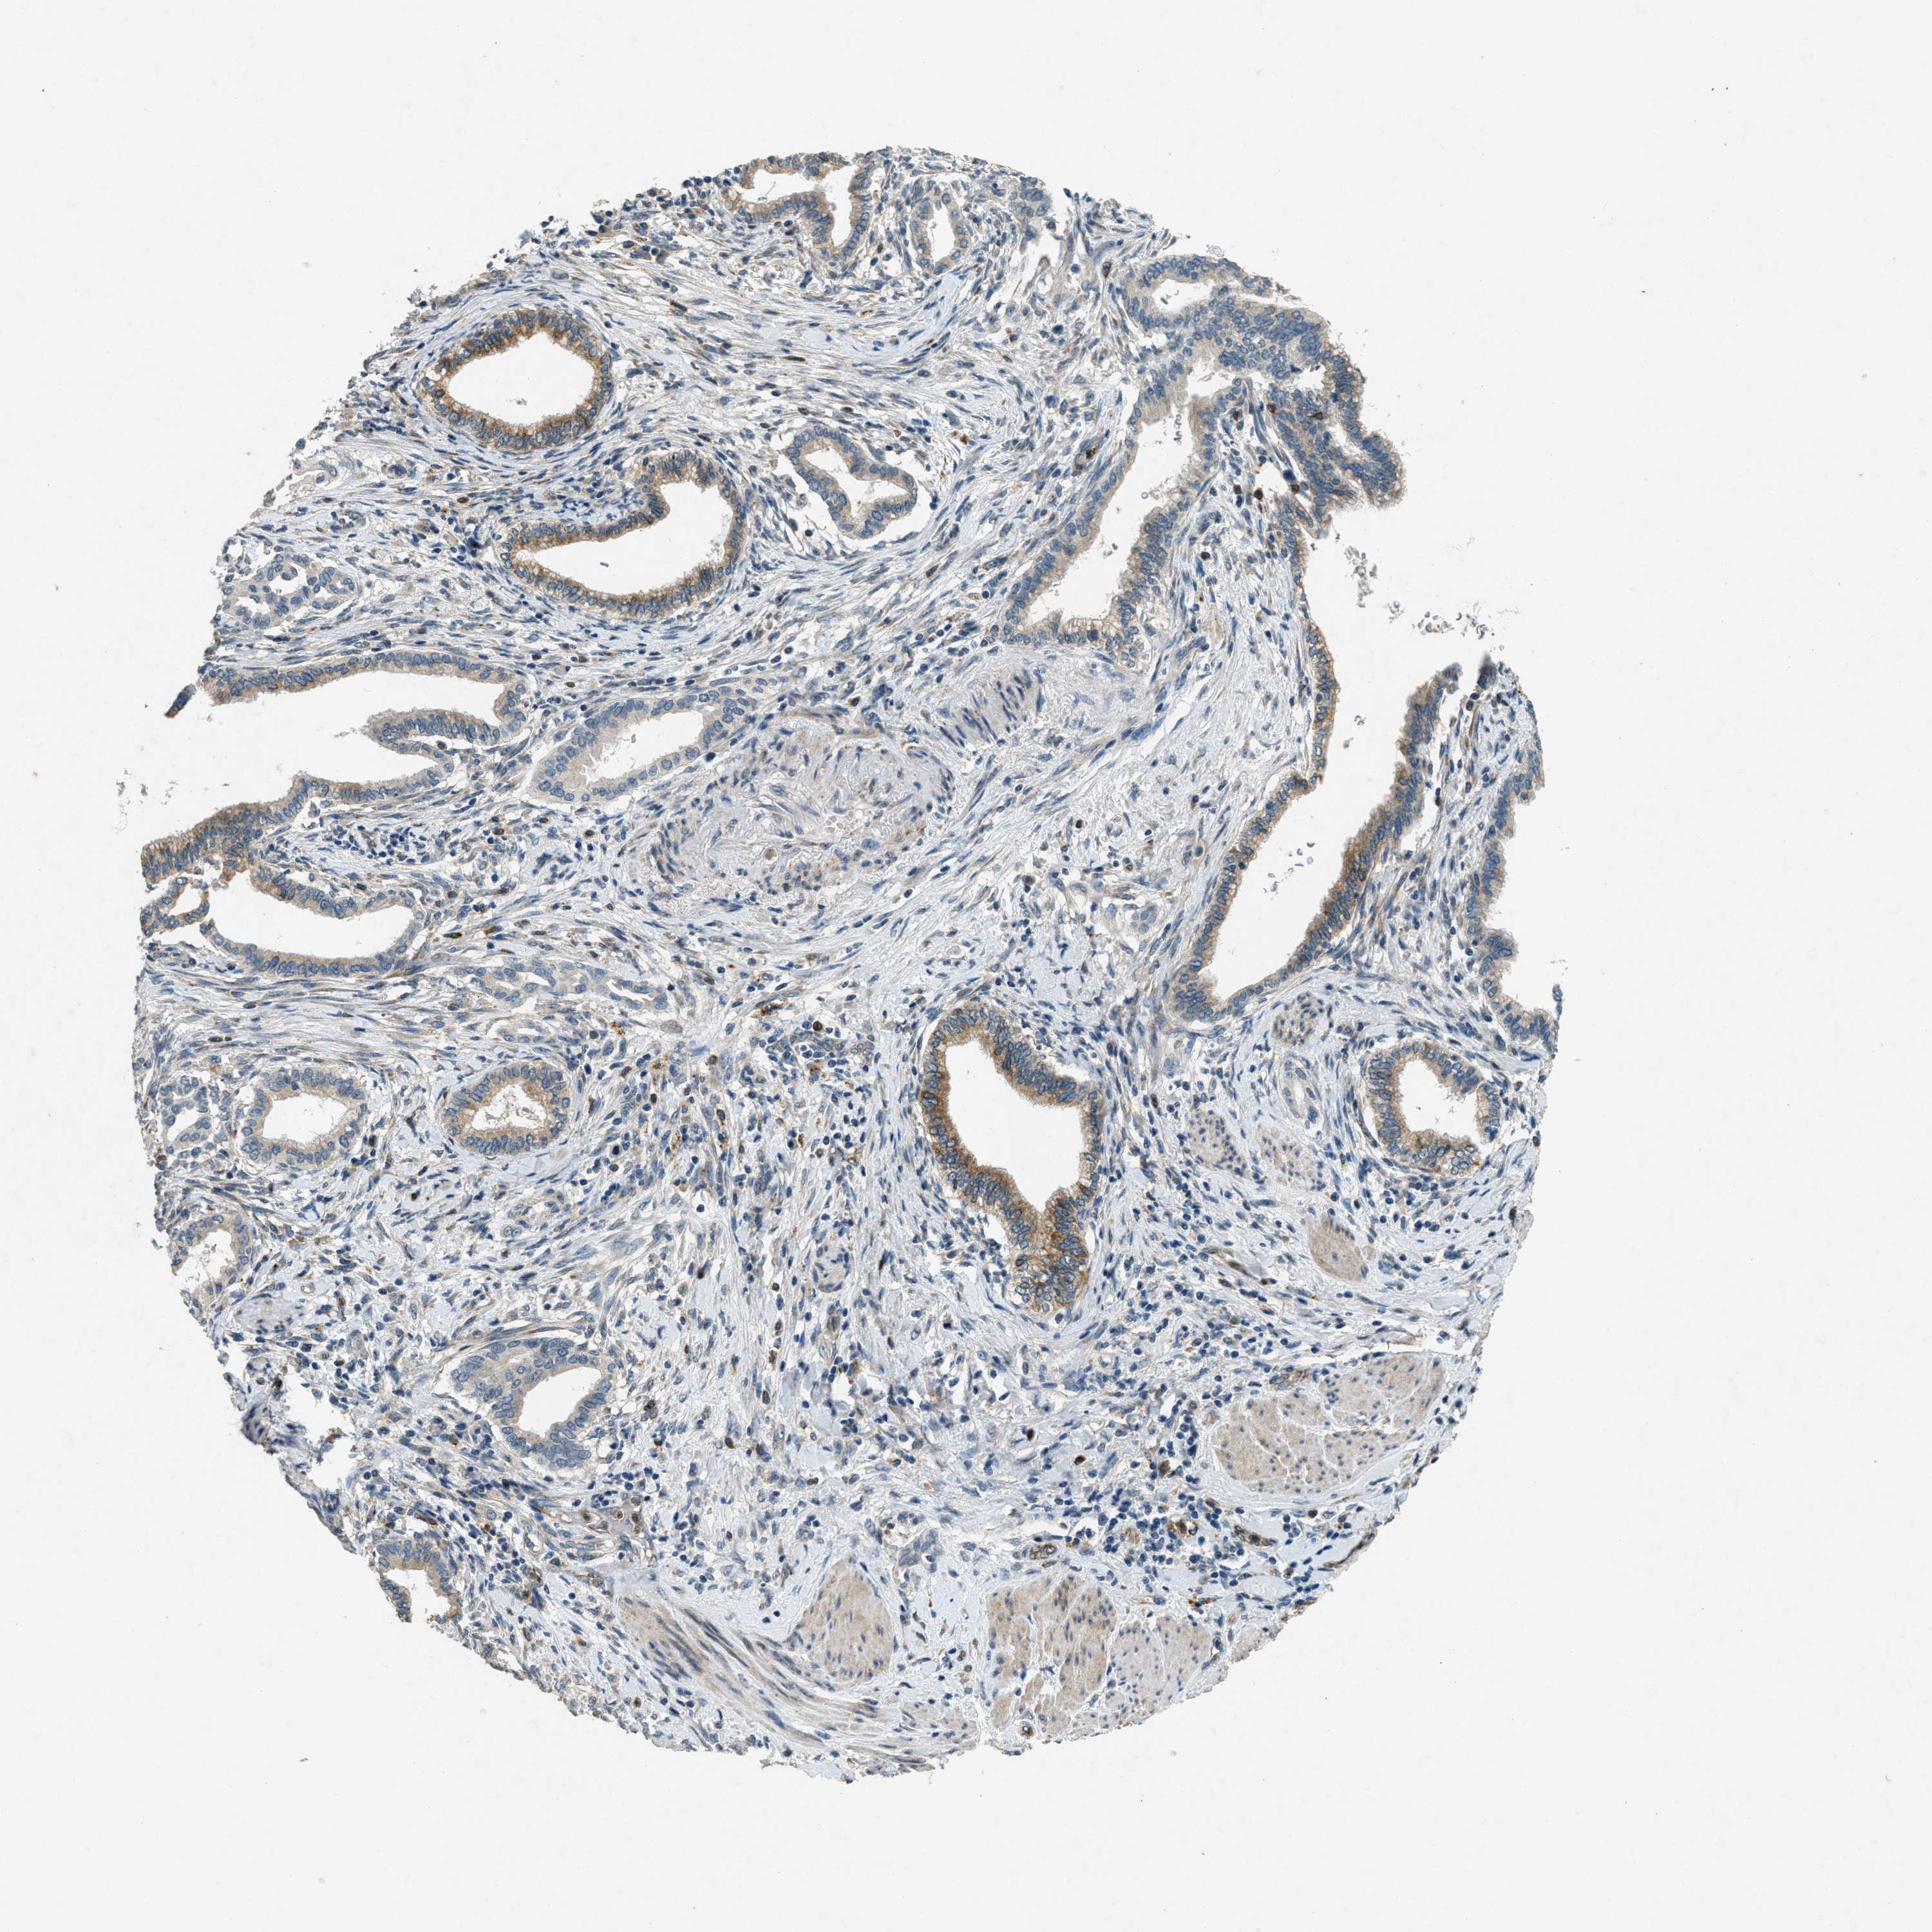

PANCREATIC CANCER - Protein expressioni

A mouse-over function shows sample information and annotation data. Click on an image to view it in a full screen mode. Samples can be filtered based on level of antibody staining by selecting one or several of the following categories: high, medium, low and not detected. The assay and annotation is described here.

Note that samples used for immunohistochemistry by the Human Protein Atlas do not correspond to samples in the TCGA dataset.

Antibody stainingi

Antibody staining in the annotated cell types in the current human tissue is reported as not detected, low, medium, or high, based on conventional immunohistochemistry profiling in selected tissues. This score is based on the combination of the staining intensity and fraction of stained cells.

Each image is clickable and will lead to virtual microscopy that enables deeper exploration of all samples and also displays staining intensity scores, fraction scores and subcellular localization as well as patient and tissue information for each sample.

Antibody CAB018067

Staining

High

Medium

Low

Not detected

Intensity

Strong

Moderate

Weak

Negative

Quantity

>75%

75%-25%

<25%

None

Location

Nuclear

Cytoplasmic/membranous

Cytoplasmic/membranous,nuclear

Adenocarcinoma, NOS

Adenocarcinoma, metastatic, NOS